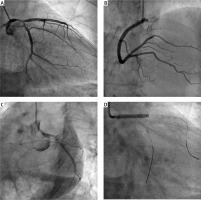

Figure 1

Acute coronary syndrome due to spontaneous coronary dissection. A – baseline coronary angiogram of the left coronary artery, B – baseline coronary angiogram of the right coronary artery, C – control angiography at the moment of the chest pain intensification showed more pronounced left main stenosis, proximal occlusion of the left anterior descending artery and 90% stenosis of the proximal part of the circumflex artery, D – percutaneous coronary intervention procedure – direct-stenting with 3.0 × 23 mm drug-eluting stent from the left main to the left anterior descending artery

Figure 1E

E - final kissing balloons inflation, F - final angiographic result, G - angio-CT with splenic artery aneurysms, H - angio-CT at 12 months with an optimal result of left main bifurcation stenting